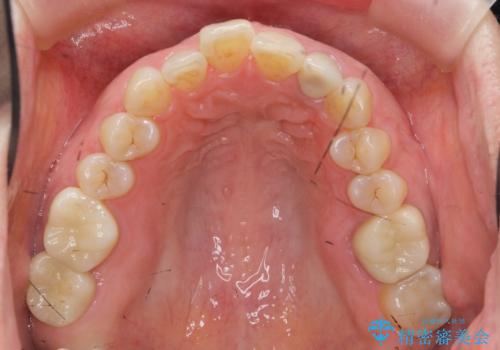

治療後、明るくなった口腔内を見て大変満足いただくことができました。

色調だけでなく、精密な治療を行うことで虫歯の再発の確率を下げることも可能になります。